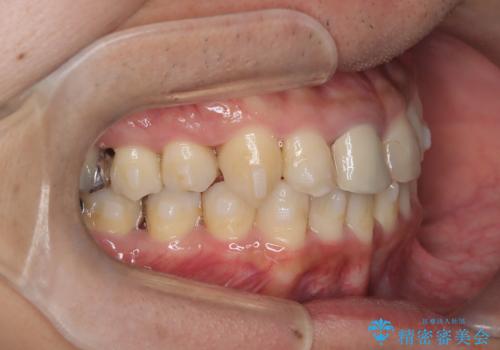

【インビザライン】八重歯と歯のでこぼこが気になる!

- 「八重歯と歯のでこぼこを治したい」を主訴に来院された患者様です。

歯は抜かずに奥歯の遠心移動とIPRで八重歯とでこぼこを改善しました。

左上3番は保険治療(CR)の劣化による二次カリエスになっていますので、後日治療予定です。